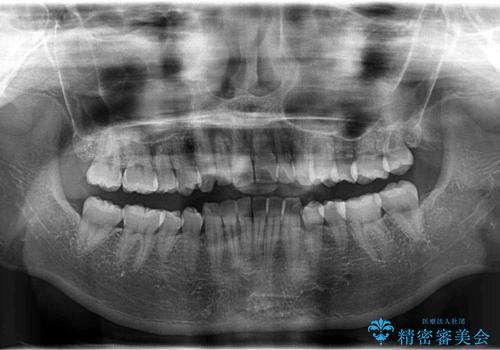

インビザラインで出っ歯を改善する 抜歯をしないinvisalign治療

- 20代女性

- invisalign full

- 1年5ヶ月

- 非抜歯・遠心移動による前突の改善をマウスピースにて計画した。

非抜歯矯正の場合、大きく前歯を下げることはできませんが、奥歯の遠心移動や歯のサイズダウンにより歯軸を立て、見かけ上の出っ歯感をある程度改善することができます。